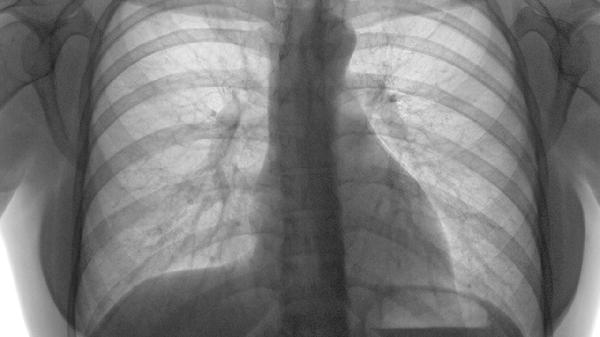

大面积肺栓塞导致血流动力学不稳定时,死亡率可达30%。通过CT肺动脉造影评估栓塞范围,累及主干动脉者需考虑溶栓治疗。